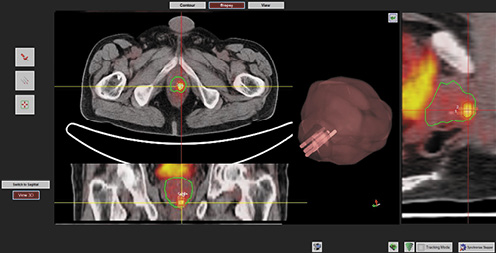

The Bio-Jet fusion system and software (D&K Technologies, Barum, Germany) will be used. The prostate profile and ROIs will be drawn on PSMA PET/CT and mpMRI and fused in real time with the TRUS image stack during biopsy. Biopsies, transrectal or transperineal according to lesion site, will be performed with patients in the dorsal lithotomy position, under antibiotic prophylaxis and local anesthesia, using 3D triplane transrectal ultrasound system (BK Medical, Analogic Ultrasound Group, Pro Focus, Transducer 8818, 6/9 MHz). Biopsy cores will be numbered according to ROI number and topography. Specimens will be processed and evaluated by a genitourinary pathologist. Tumor foci will be quantified and graded according to the ISUP consensus conference on Gleason grading (Fig. 1).